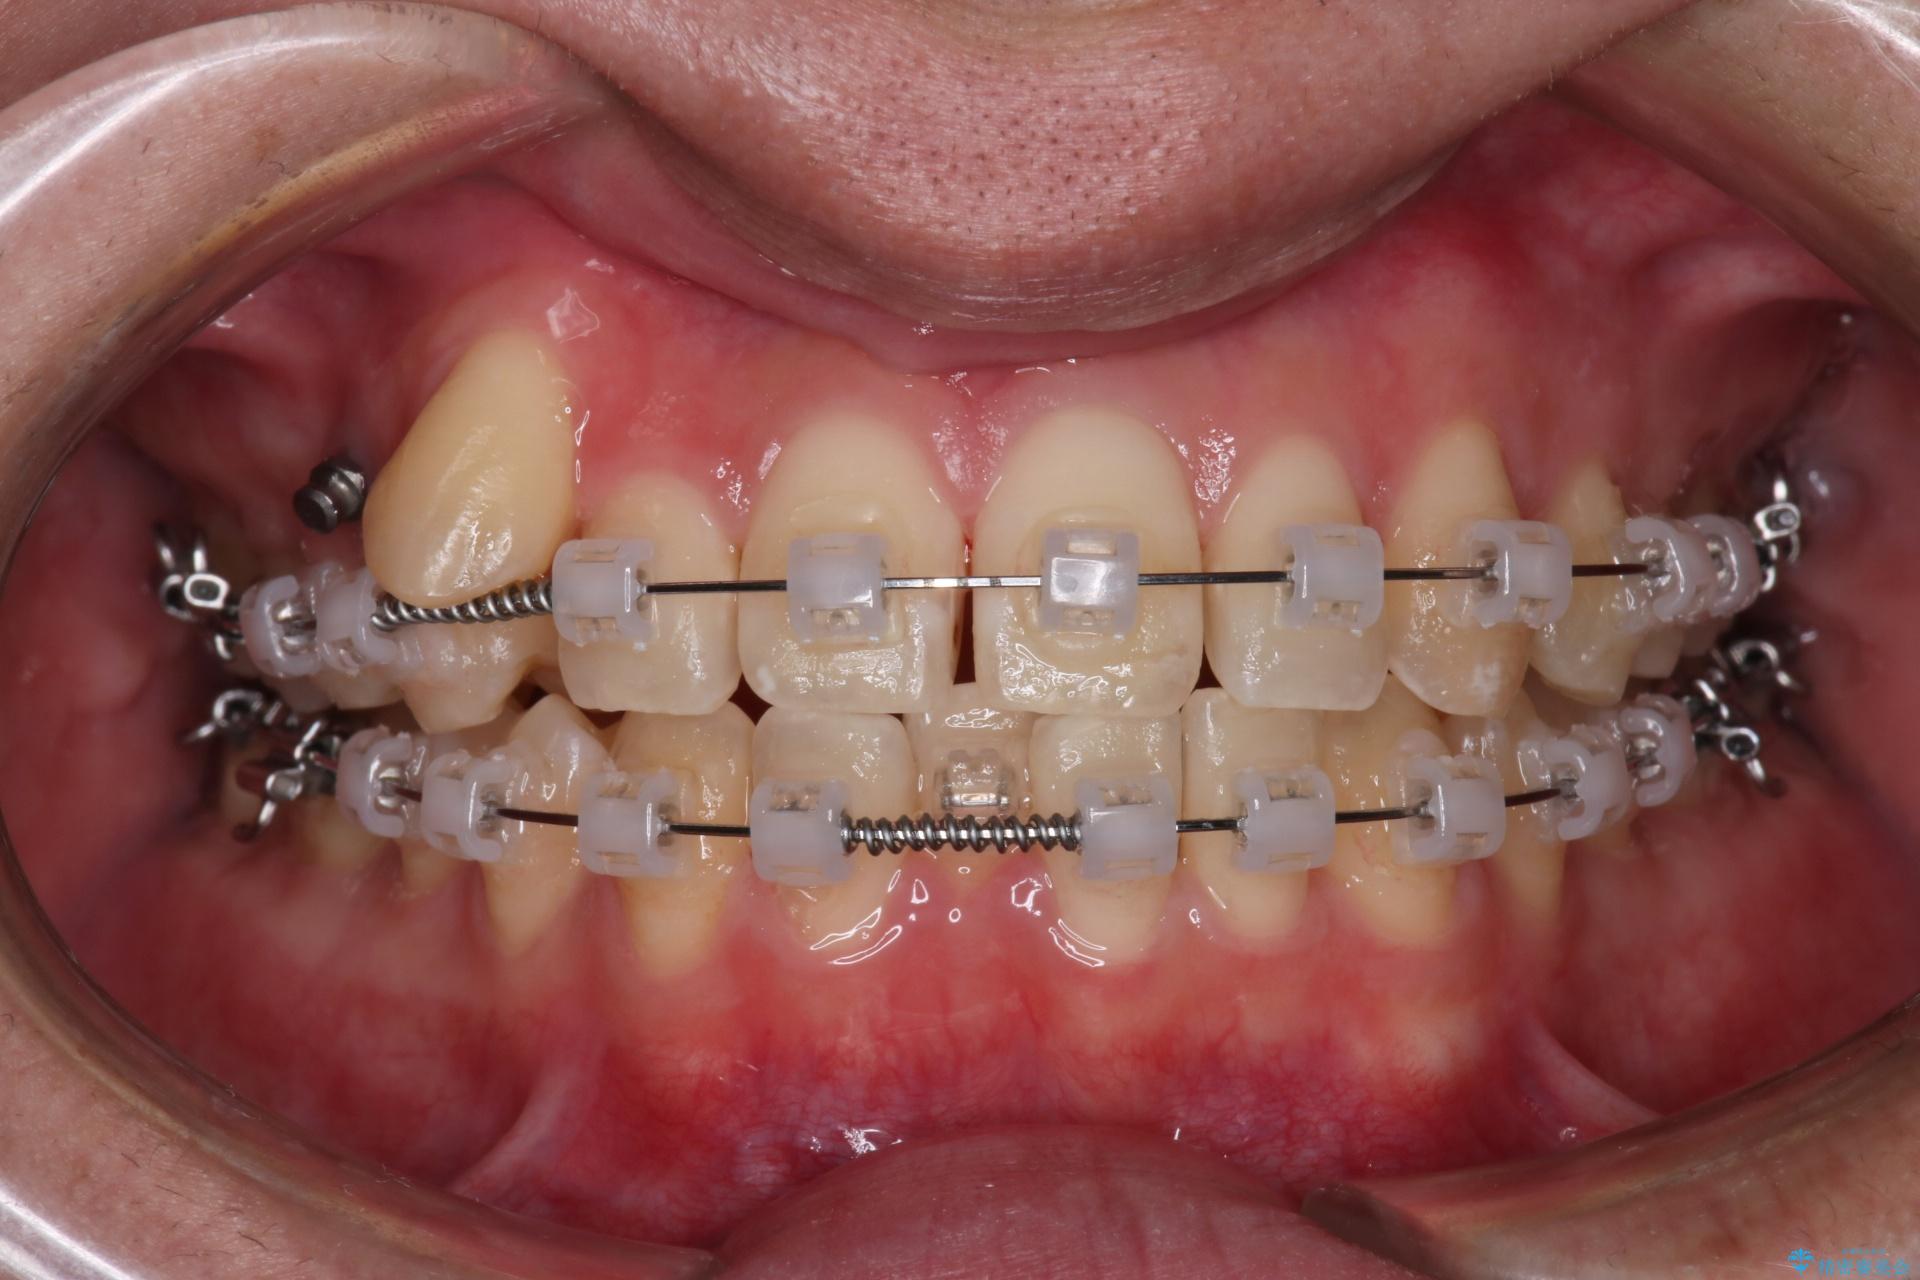

目立ちにくいクリア装置で八重歯とがたつきの改善

歯の移動にオープンコイルとMI(歯肉に埋入するネジ)を用いました。

非抜歯での治療だったため、1年半以内という短い期間で矯正を終了することができました。主訴であった八重歯とがたつきが改善され、大変ご満足いただきました。